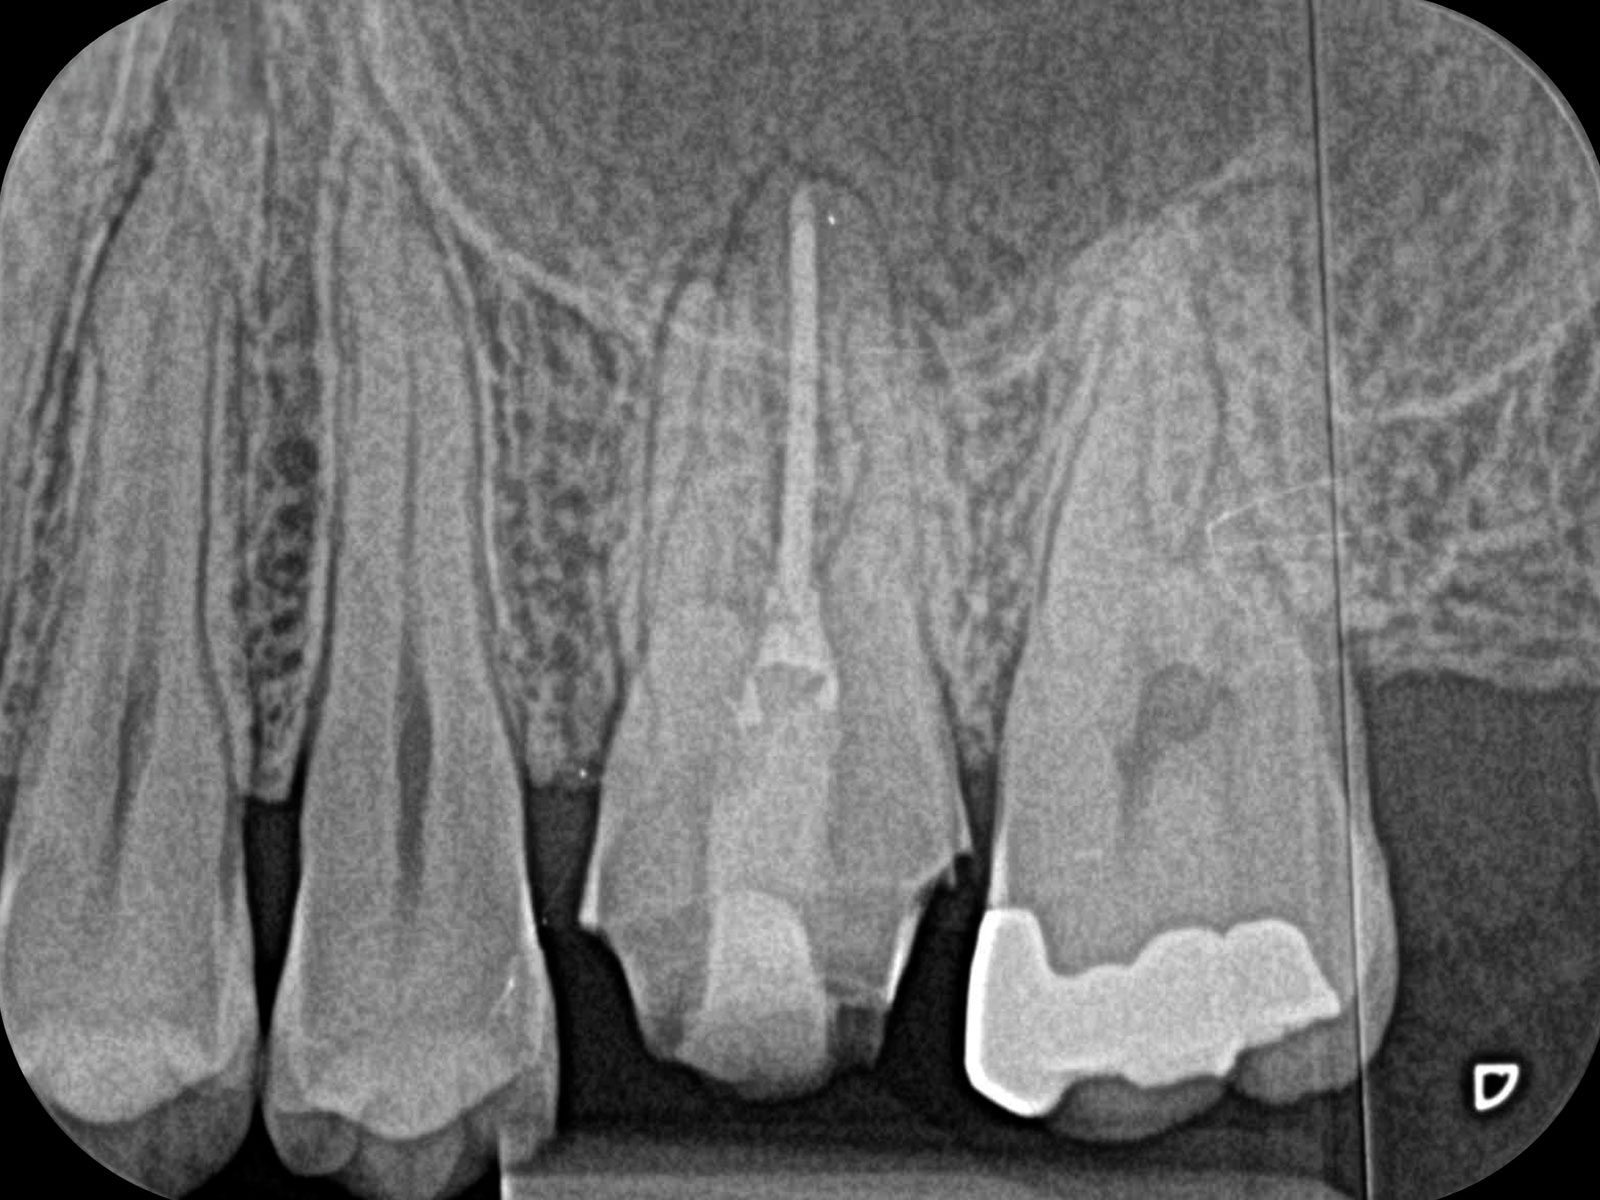

主訴: 右下がしみて痛い。

右下7根の根幹治療と親知らずの抜歯